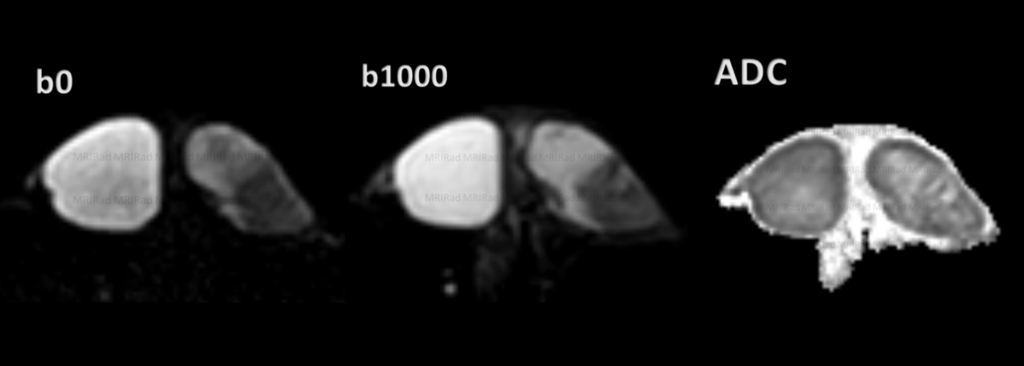

4. DWI σε εγκάρσιο επίπεδο με τουλάχιστον 3 τιμές b value (0, 400-500, 800-1000 s/mm2). Η ελάχιστη και η μέγιστη τιμή χρησιμοποιούνται για τον υπολογισμό του χάρτη φαινομενικού συντελεστή διάχυσης (ADC map).

Χαρακτηριστικές Εικόνες MRI Οσχέου

iii) DWI (ADC)

Βασική Ακτινοανατομία MRI Οσχέου